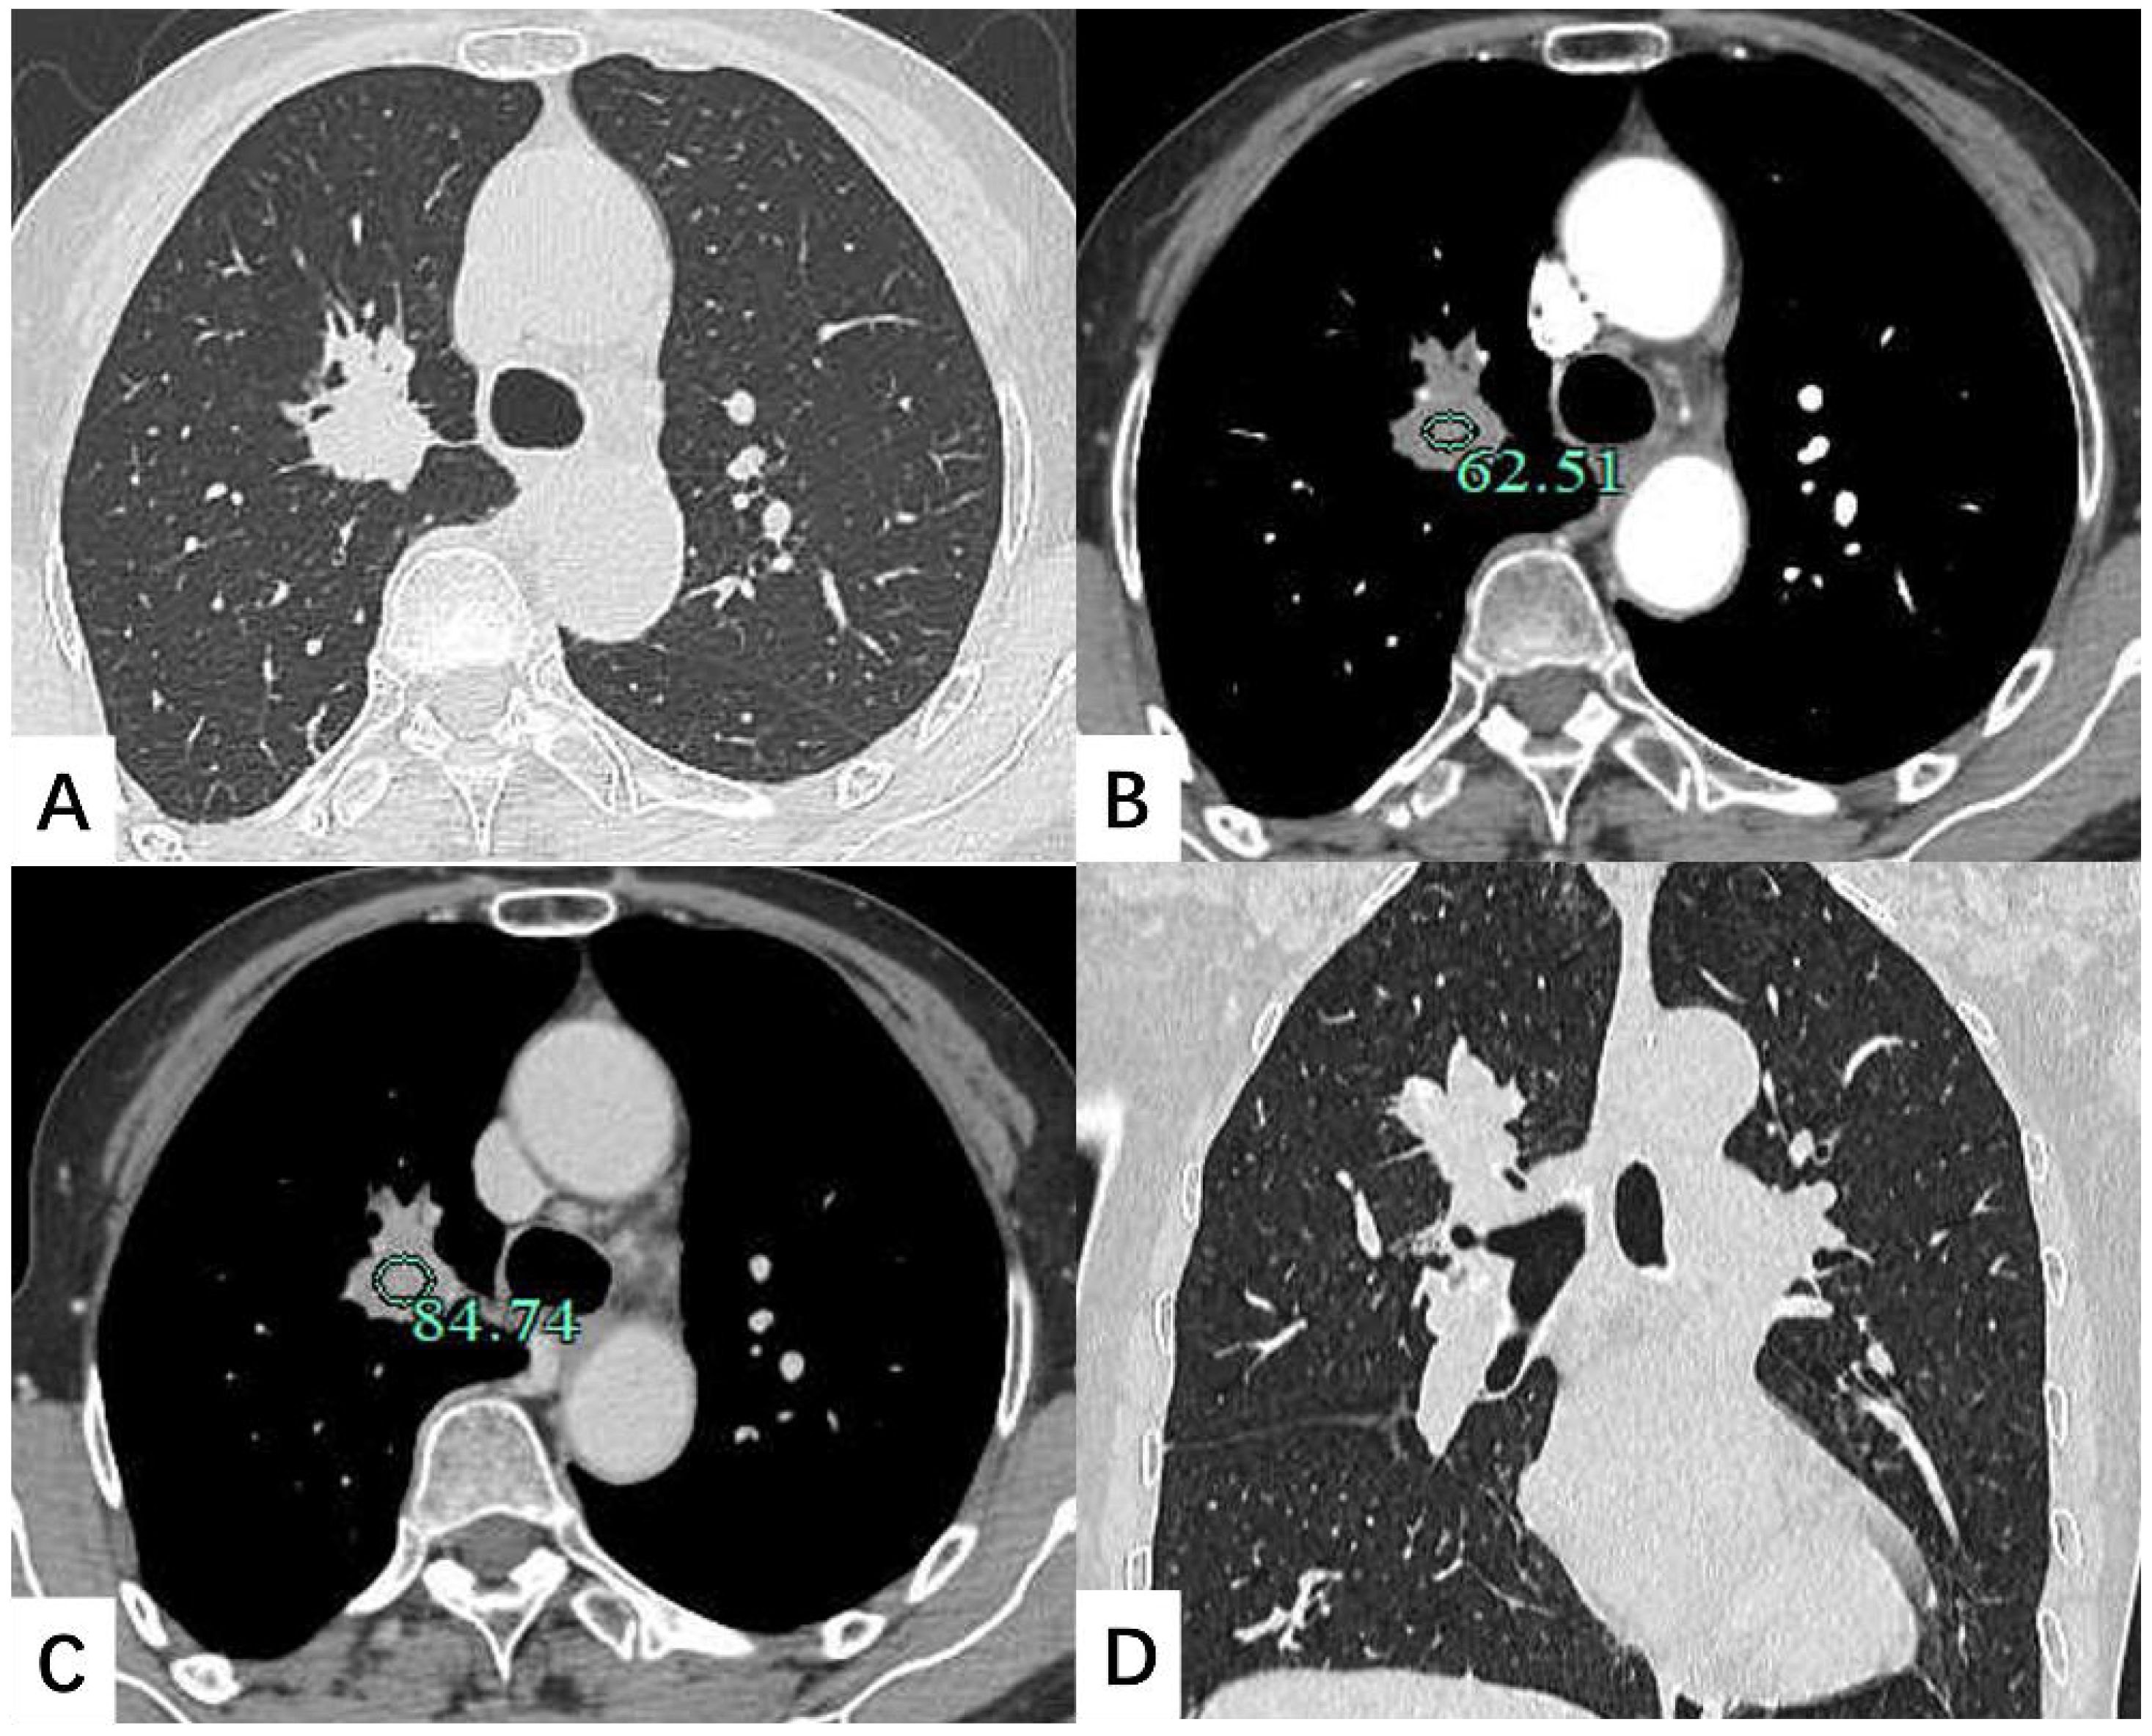

A contrast-enhanced chest CT scan revealed a 30 × 25 mm nodule in the lung RUL, characterized by spiculated margins and proximal bronchial atresia, findings suggestive of lung cancer (Figure 1). Enlarged right hilar lymph nodes were also observed. Bronchoscopy demonstrated obliteration of the tip segment of the lung RUL, with mucosa appearing edematous. Endobronchial ultrasound revealed hypoechoic shadows within the right lung that exhibited uniform internal echoes. Bronchoscopic biopsy showed fibrous exudate containing scattered lymphocytes and glandular epithelial cells.

Figure 1. Contrast-enhanced chest CT scan depicted a 30 × 25 mm soft tissue nodule located in the lung right upper lobe. The shadow exhibited mild enhancement on the enhanced scan. (A) Transverse position CT plain scan; (B) Transection CT scan arterial phase; (C) Transection CT scan venous phase; (D) Coronal position CT scan.